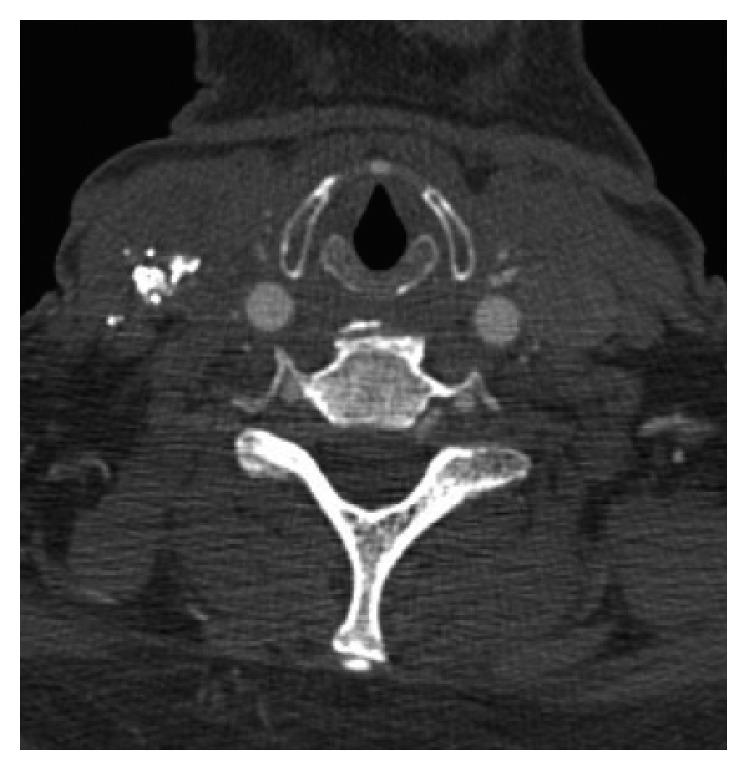

A 63-year-old female with multiple comorbidities presented with a firm 7 cm tender mass located in the right neck. Ultrasound showed pseudoaneurysm and a 7 × 3.3 × 4 cm multilobular hematoma in the location of the previous central line. CTA showed a corresponding heterogeneous mass. Serial imaging demonstrated enlargement over 2 weeks. Angiogram showed contrast blush off of the SBSTA.

一名患有多种合并症的63岁女性,右颈部出现一个质地坚硬、压痛的7厘米肿块。超声显示假性动脉瘤以及位于先前中线位置的一个7×3.3×4厘米的多叶血肿。CT血管造影(CTA)显示有一个相应的不均匀肿块。连续成像显示该肿块在2周内增大。血管造影显示SBSTA有造影剂外溢。